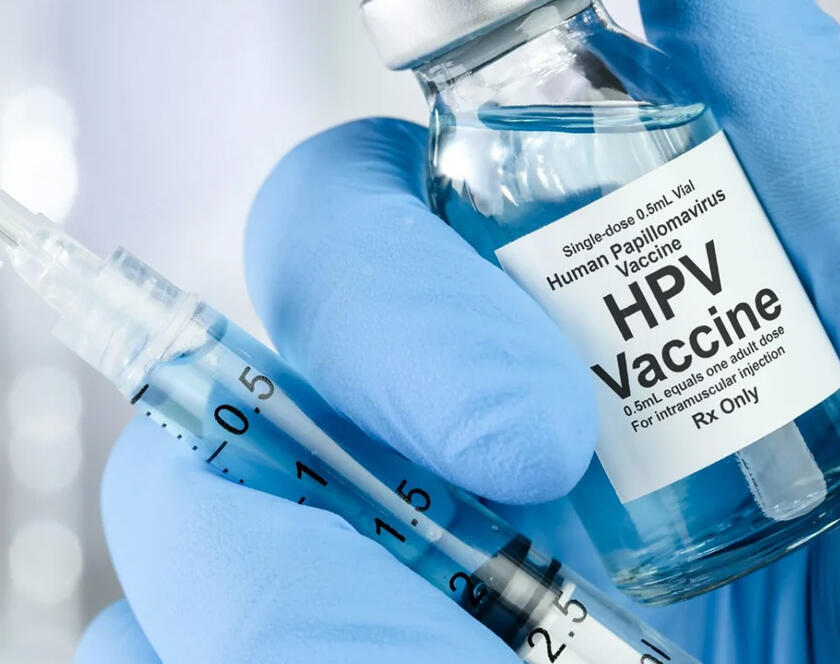

HPV Vaccines: A Shield for Your Health and Future Human Papillomavirus (HPV) is one of the most common infections, with certain strains leading to cervical cancer. At Livf, we believe…